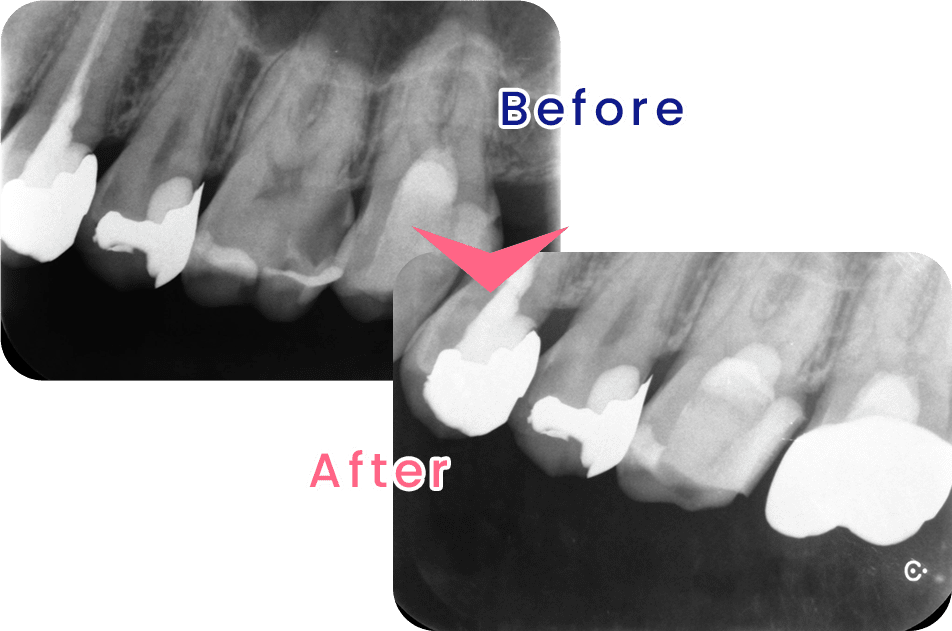

米国の歯内療法専門医が行う術式による治療です。先端設備と高度な治療を用いることで、従来の根幹治療では治療が難しかった症例でも、歯を残すことのできる確率を高めることが可能になります。

患者様に、より多くの選択肢からご自身に合ったものをお選び頂きたいと考え、インプラント治療を実施しております。インプラントとは、歯を失った顎堤に人工歯根を埋め込み、人工歯を取り付ける治療です。

当院のインプラント治療